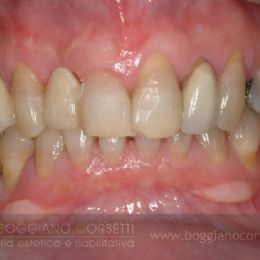

Il seguente caso è complesso, con problemi da risolvere non è solo a livello dei vecchi restauri difettivi (laterali, premolare, ponte oro-resina inferiore), ma anche per le irregolarità livello gengivale e occlusale

Interventi chirurgici e ortodontici hanno ottimizzato le parabole gengivali e l’allineamento dentale.

Notate come, nel lavoro finito, l’estetica dentale e quella gengivale insieme contribuiscano a creare una condizione di armonia e di equilibrio tra le sue componenti.

Un difetto nei tessuti circostanti, infatti, non può essere compensato dalla qualità del restauro dentale e viceversa.